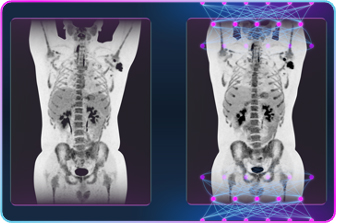

Omni Legendは,全身腫瘍検索,アミロイドPET,Theranostics(セラノスティックス)などPET/CT検査におけるこれらニーズに応えるべく設計された全く新しいプラットフォームを持つPET/CT装置です。カッティングデザインを一新したシンチレーターおよび半導体SiPMで構成された最先端検出器により,超高感度・高分解能を実現し,高画質の提供は勿論,短時間および微量のアイソトープでの画像化によって,検査スループットの向上と被検者の被ばく低減を可能とします。

また,AI技術を駆使したPrecision DL,ディープラーニング3Dカメラにより,診断の確信度の向上とワークフローの簡素化による検査効率の向上も追求しました。